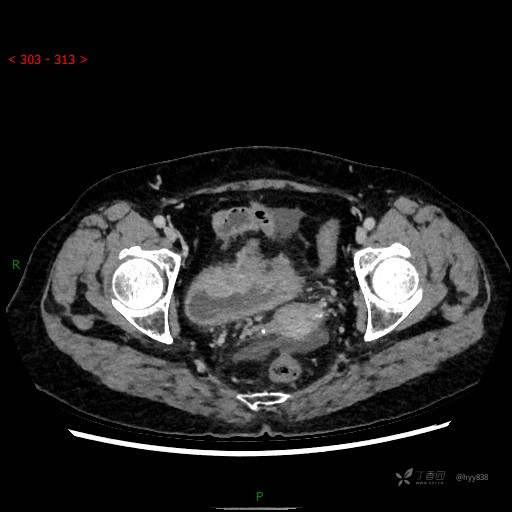

辅助检查:CT

增强(2022.11.1)